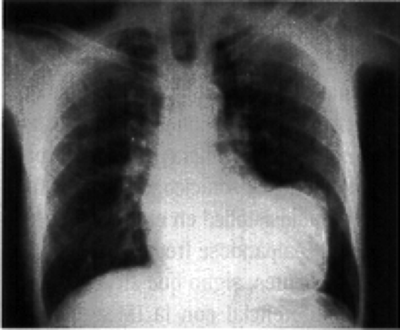

Paciente de sexo femenino, de 30 años aproximadamente, acusa antecedentes de obesidad tabaquismo sumado a una hipertensión arterial. Se presenta radiografía de corazón. ¿Cuál es su diagnóstico?

Answer

• Un aumento del tamaño de la silueta cardíaca a expensas del ventrículo derecho y contracción aórtica.

• Cardiopatía Hipertensiva sumado a un aumento del tamaño de la silueta cardíaca a expensas del ventrículo izquierdo y elongación aórtica.

• Miocardiopatía restrictiva caracterizada porque el corazón se vuelve muy rígido y tiene dificultades para llenarse.

• Miocardiopatía restrictiva. caracterizada porque el corazón se vuelve muy flexible teniendo dificultades en el bombeo de sangre.